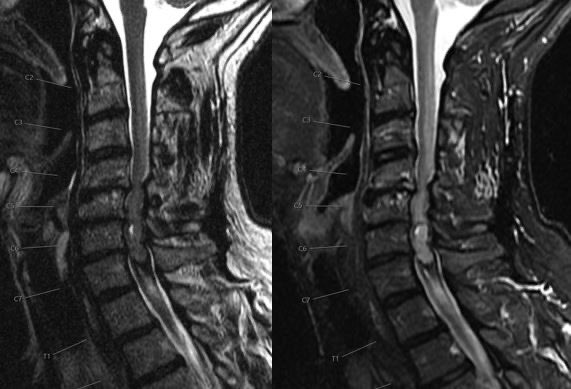

What is the most likely diagnosis in this 65 y/o M presenting w/ leg weakness, hyperreflexia, spasticity and absent vibration sense in the LE? #neu